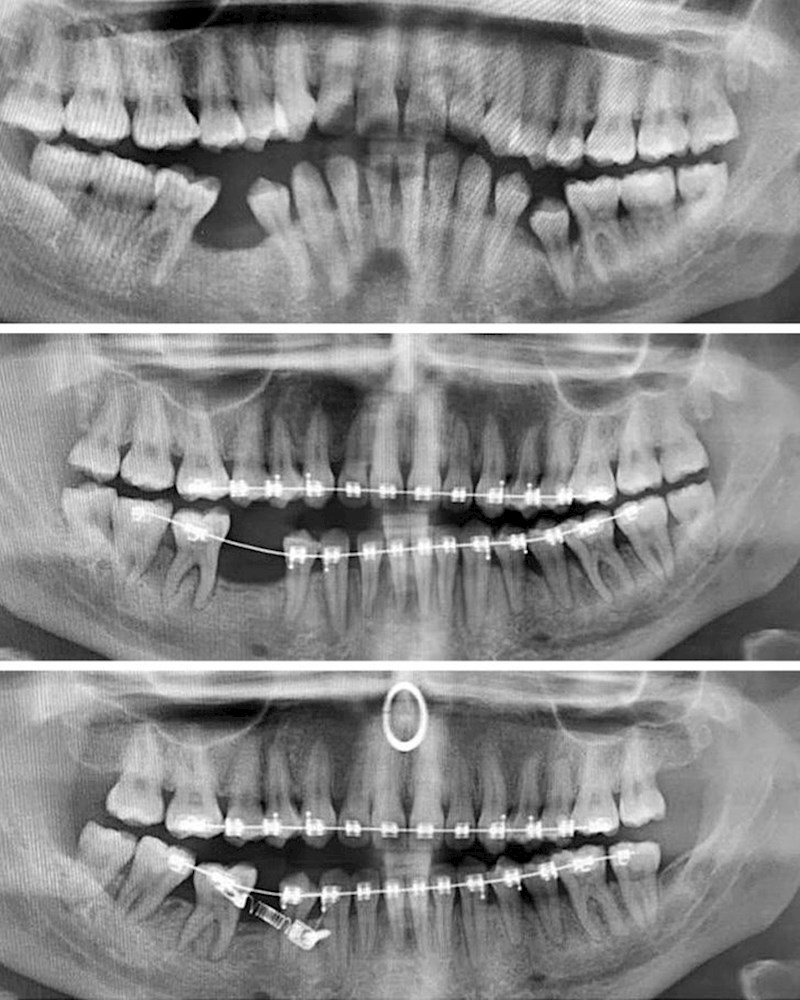

Ispravljanje zubi u razmaku od 2 godine